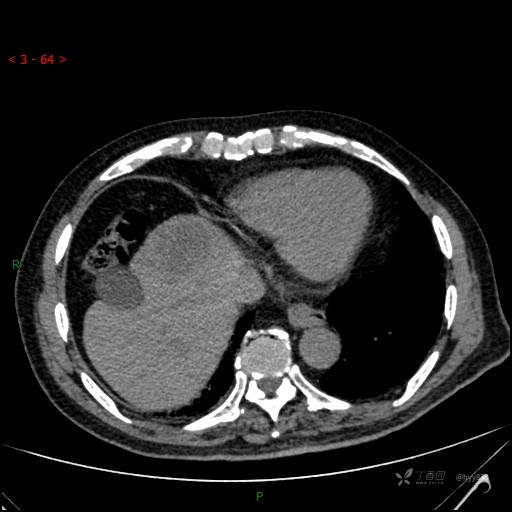

肝脏CT平扫

img